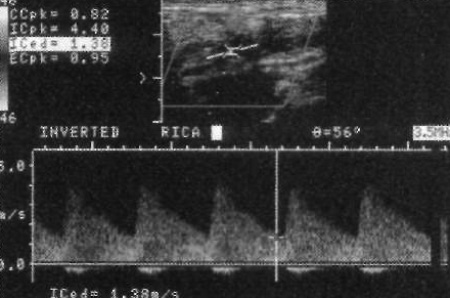

Важно, чтобы врач сопоставлял имеющиеся данные с размером сосудистого просвета, который визуализируется на цветовой допплерографии (фото 4).

Фото 4. Тяжелый стеноз внутренней сонной артерии. Максимальная систолическая скорость – 4,4 м/с, увеличение конечно-диастолической скорости до 1,38 м/с; соотношение скоростей потока во внутренней сонной артерии и общей сонной артерии составляет 5,4

Уменьшение просвета сосуда < 50% не влияет на показатели конечно-диастолической скорости в области стеноза. Если стеноз > 50%, диастолическая скорость увеличивается пропорционально сужению сосудистого просвета, что обусловлено возникновением градиента давления в диастолу. При стенозе > 70% конечно-диастолическая скорость резко увеличивается (фото 4 и фото 5).

Показатель отношения систолических скоростей увеличивается пропорционально тяжести стеноза. Так, отношение 2 соответствует стенозу > 50%, отношение 3 – стенозу > 75% (фото 4 и фото 5).